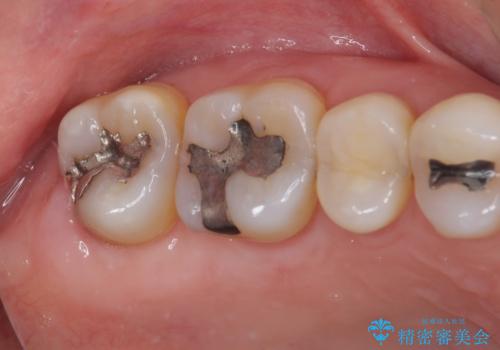

- 奥歯に装着されてい銀歯の中が虫歯になってしまったとのことで来院された患者様です。

虫歯をしっかりと取り除き、ゴールドインレー(PGAインレー)にて修復することとしました。